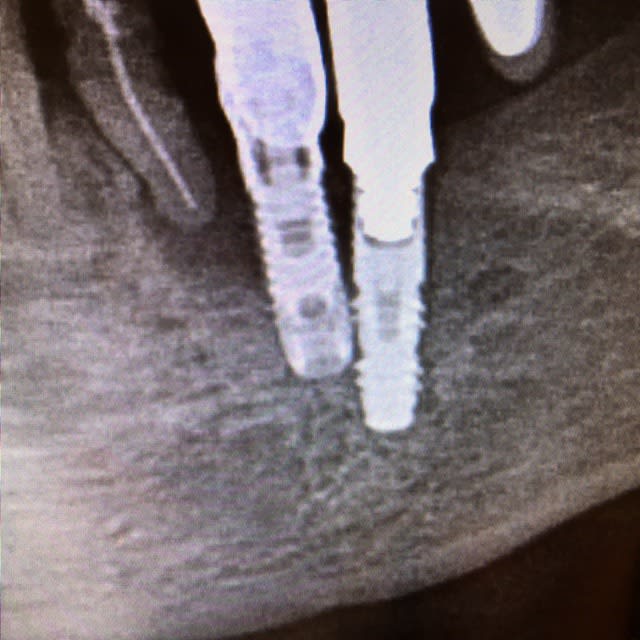

est ce que cette rd peut t'aider ?

dommage il n'y a pas l'apex...

mais il me semble distinguer le filetage dans le pilier

disons que çà affine...;-)

j'en suis de moins en moins sûr...les spires ne ressemblent pas à celles des screwvent...

ce qui ressemble le plus à ce type de spires c'est les vieux sterioss...

mais je ne trouve pas d'implants dans cette marque avec une connexion ressemblante...

donc...une meilleure radio?

sur celle ci on voit un peu mieux l'apex !!